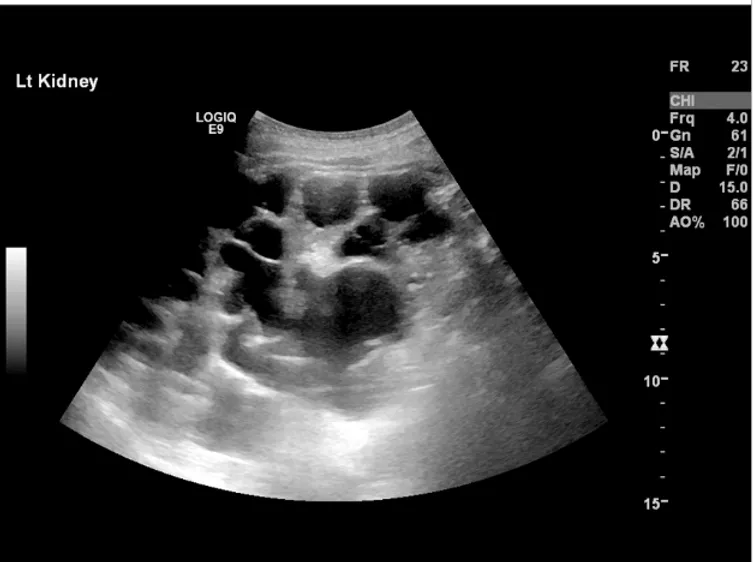

Este vídeo apresenta, de forma didática e baseada em evidências, os principais achados da tese de doutorado sobre amiloidose renal, com foco em proteômica glomerular e ativação do complemento. São discutidos aspectos diagnósticos, implicações fisiopatológicas e correlações clínico-patológicas relevantes para a prática do nefrologista. O conteúdo sintetiza dados inéditos de matriz extracelular glomerular e diferencia perfis entre subtipos de amiloidose. Trata-se de um material aprofundado e acessível, ideal para atualização de especialistas na área.